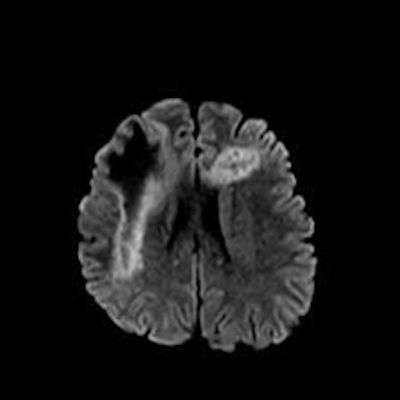

2. B) Aksiyel diffüzyon ağırlıklı serilerde bilateral sağda belirgin frontoparietal subkortikal ve derin periventriküler beyaz cevherde periferal DAG hiperintens ADC hipointens, hafif diffüzyon kısıtlaması (oklar) eşlik etmektedir. IVKM sonrası kesitlerde tarifli alanlarda belirgin kontrast tutulumu (oklar) izlenmedi.

3. Kontrastlı incelemelerde genellikle kontrast tutulumu izlenmez. Diffüzyon görüntülemede özellikle lezyonun ilerleyen periferik alanlarında yamalar halinde diffüzyon kısıtlılığı izlenir. MR spektroskopide NAA azalması, laktat varlığı ve artmış kolin ve lipid düzeyleri görülür. MR perfüzyonda ise lezyonların ilerleyen kenarında perfüzyon artışı saptanabilir.

4. Bizim hastamızda bilinen HIV enfeksiyonu mevcuttu ve yapılan kraniyal MR görüntülemede multifokal, asimetrik, periventriküler ve subkortikal beyaz cevherde yerleşimli, kitle etkisi göstermeyen ve kontrastlanmayan lezyonlar izlendi. Lezyonların subkortikal U-fiberleri tutması ve özellikle parieto-oksipital bölgelerde belirgin olması nedeniyle ön planda PML düşünüldü. Histopatolojik tetkik ile PML tanısı doğrulandı.